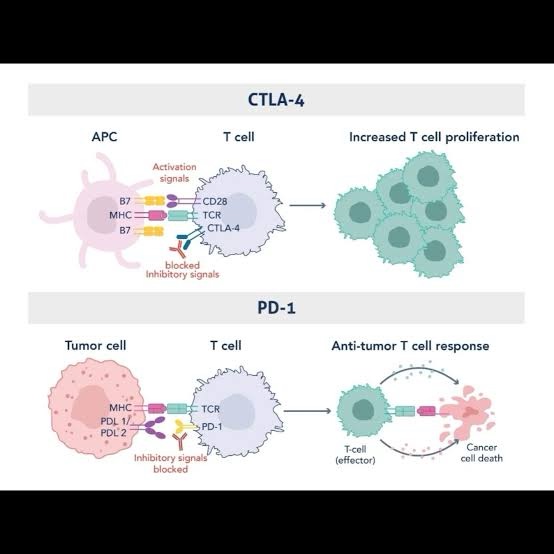

What are each of the doses of IpiNivo doing biologically?

Why do Oncologists only use 4 doses of IpiNivo in the treatment of Metastatic Melanoma?